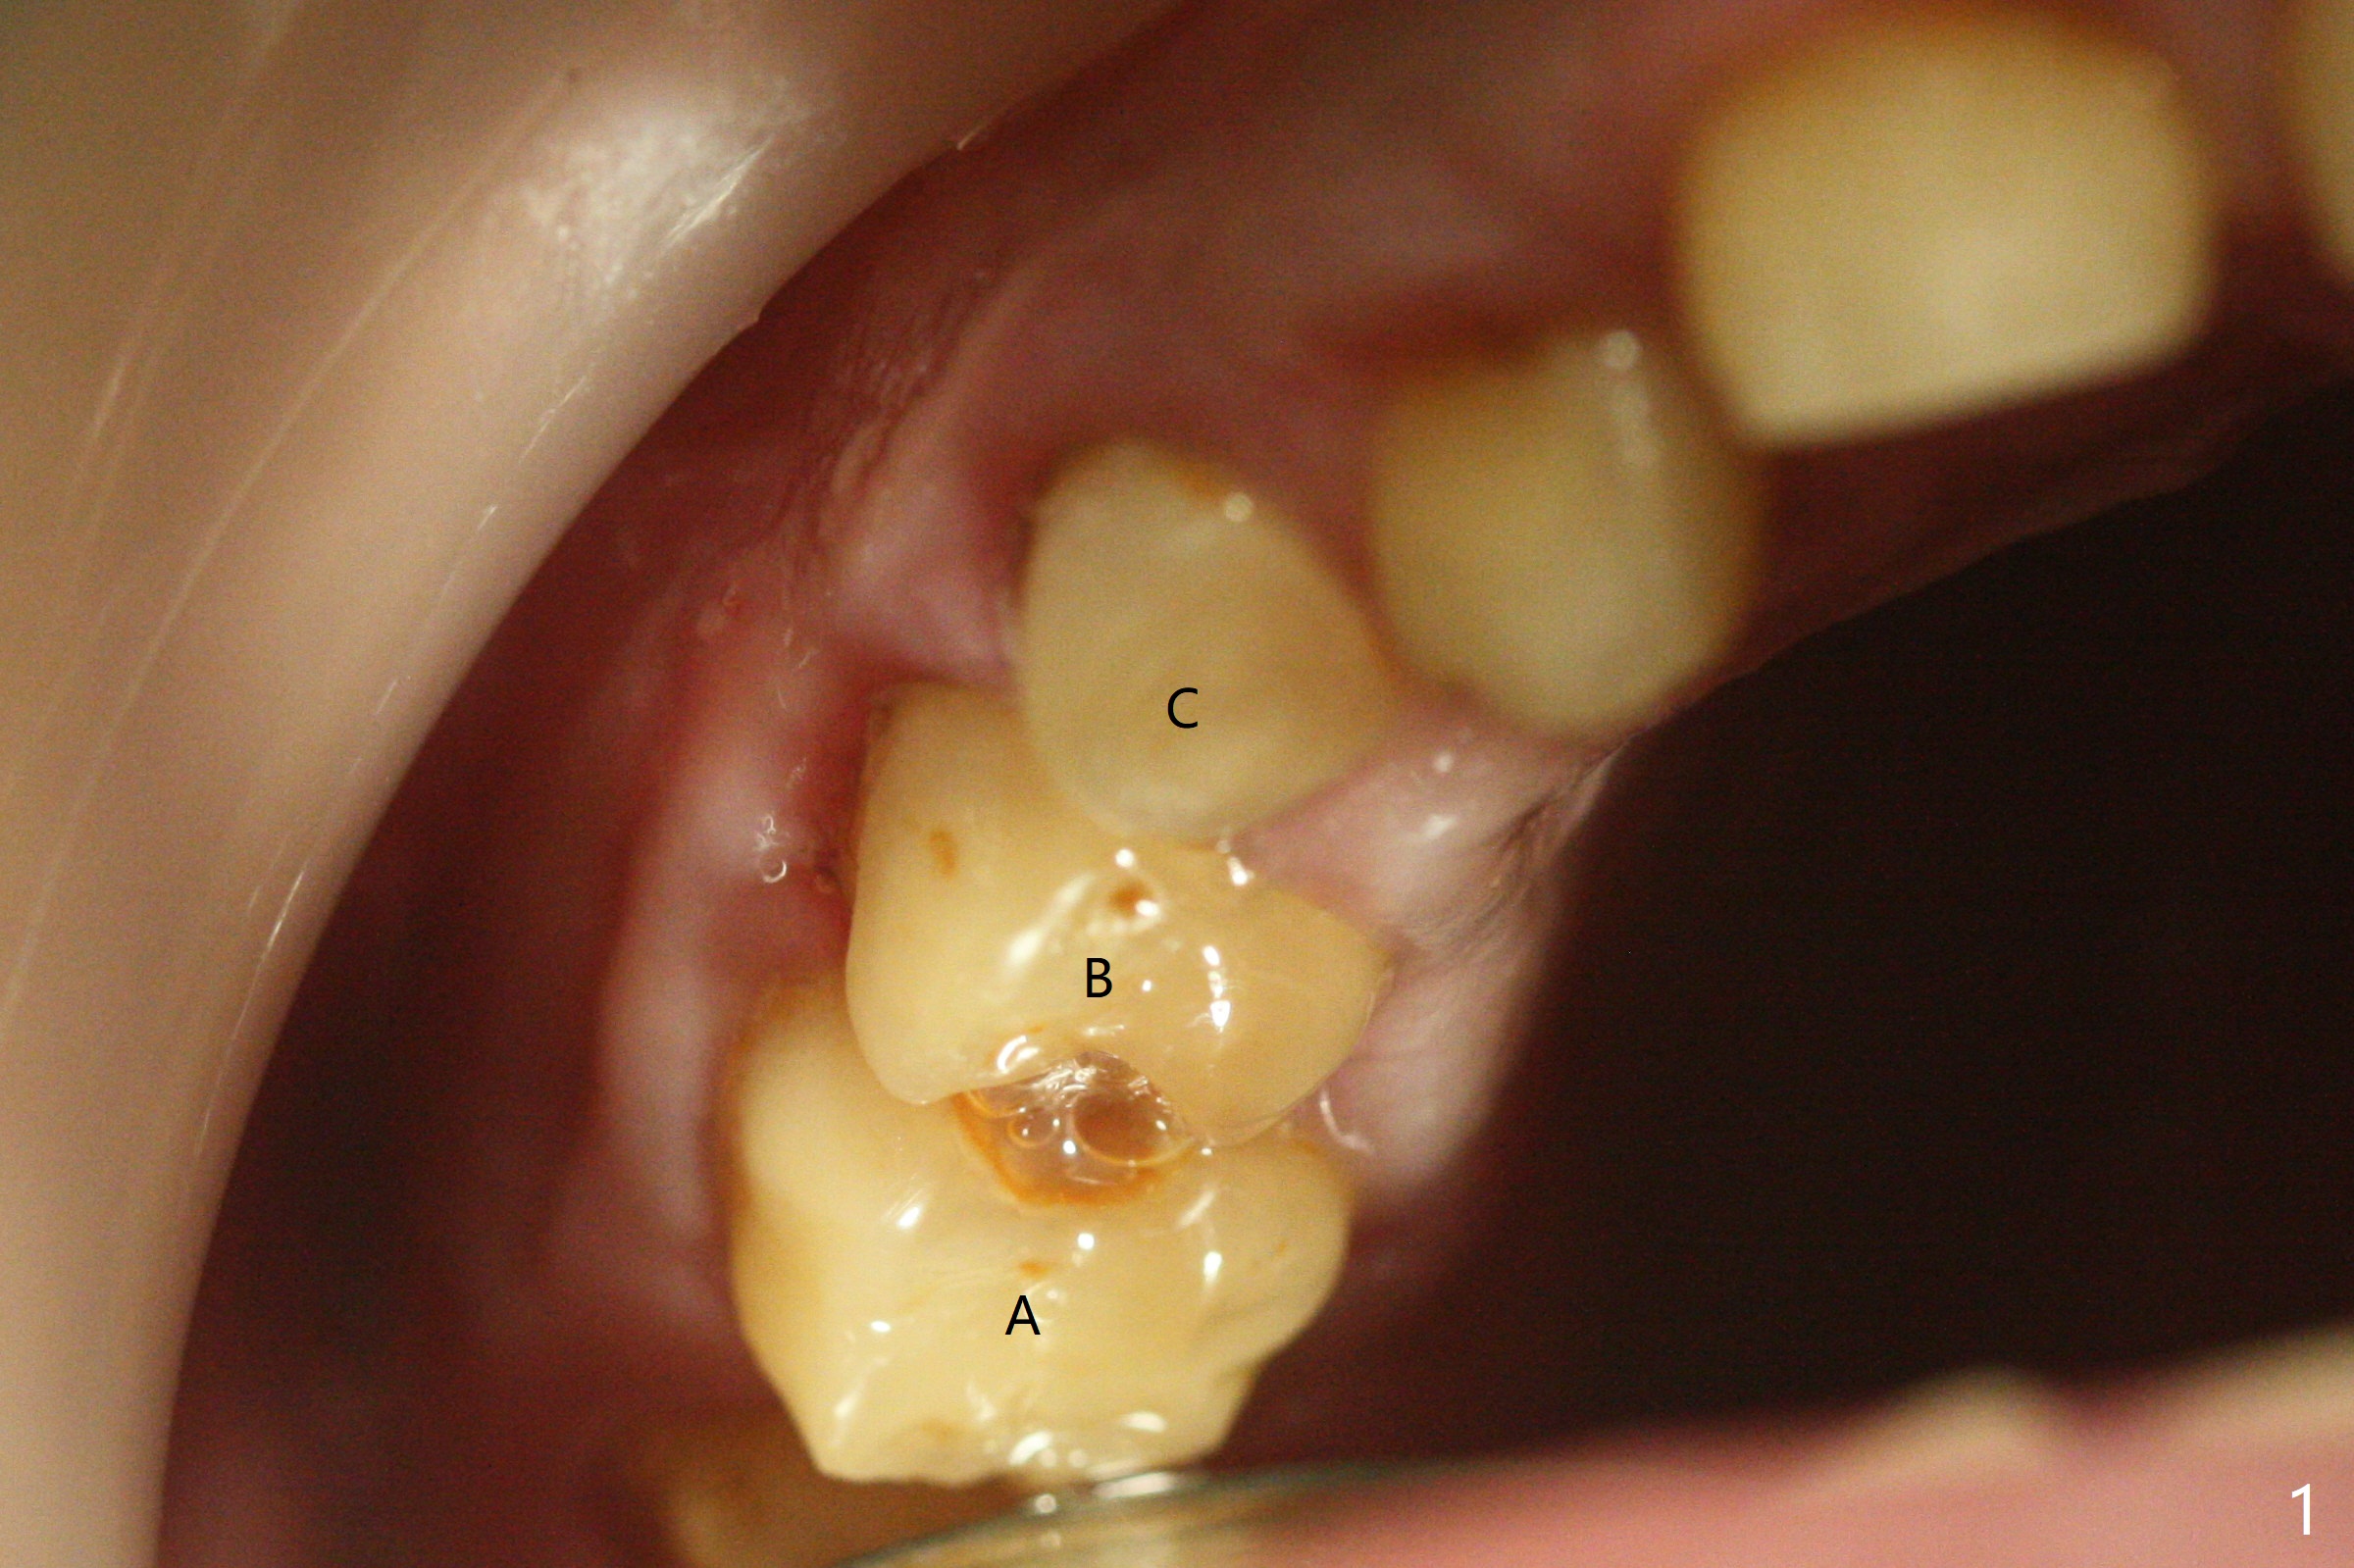

13岁男孩,每颗乳恒牙交换时乳牙都需要拔除,萌出的恒牙个子小,侧切牙反合(图二,五),对冷热敏感,不爱刷牙,口腔卫生欠佳(图三:13(结石)),父母要求诊治。今天在局麻下,左上洁治,没有局麻区域无法洁治,敏感,并且拔除H-J。S下沉,5,28埋伏(图七),其余乳磨牙都有龋齿。如何治疗?是釉质发育不全?暴露5,28前将拍摄CT。